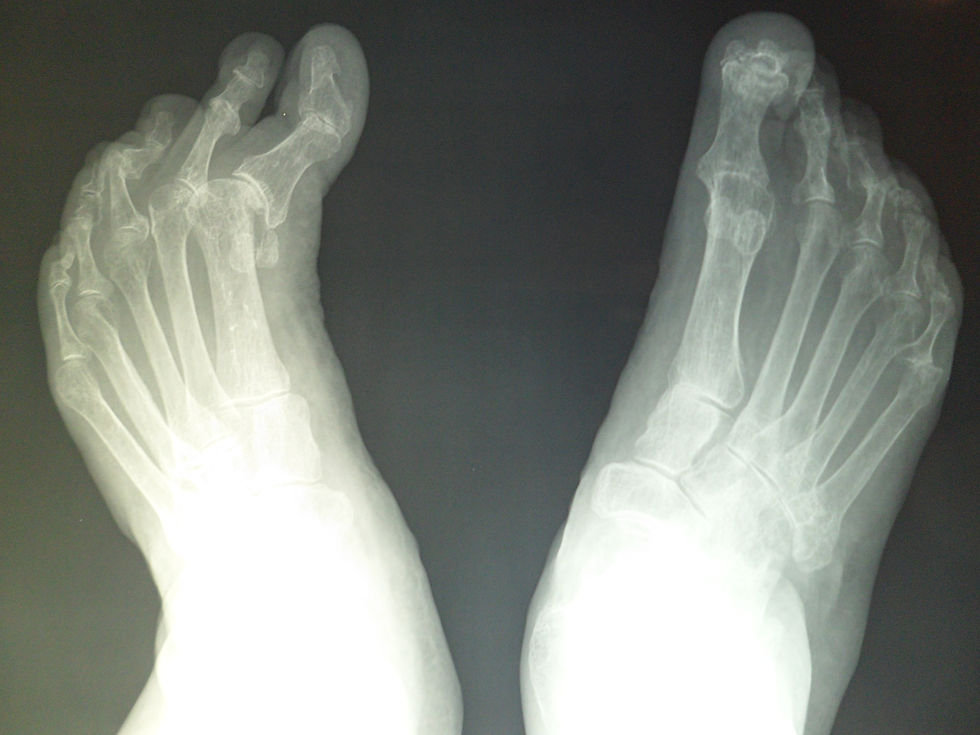

Deformidades de los pies

Deformidades de los dedos